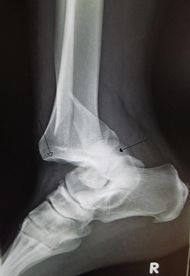

| An traumatic dislocation of the tibiotalar joint of the ankle with distal fibular fracture. Open arrow marks the tibia and the closed arrow marks the talus. | |

الخَلْع Joint dislocation يحدث عندما يتحرك أي عضو من الجسم من مكانه الطبيعي. وعندما يحدث الخلع في العظام، لا تلتقي في المفصل كما ينبغي، وينتج عن هذا في الغالب ألم وتورم.

وقد تخرج عظام مفصل مابشكل خفيف من مكانها، ويسمِّي الأطباء هذه الحالة ماتحت الخلع أو الخلع الجزئي. وفي حالات أخرى تصبح العظام منفصلة تماماً عن بعضها بعضًا. وهذا يسمى الخلع الكامل. يصحح الطبيب الخلع بتحريك العظام لإعادتها إلى موقعها الطبيعي، ويسمى هذا الإجراء رد الخلع، ويمكن لبعض المفاصل المخلوعة أن تعود إلى وضعها بشكل طبيعي. وفي الخلع البسيط، يشاهد لدى المريض جرح خارجي، أما الخلع المركب فهو الذي يصحبه جرح مفتوح على سطح الجسم. وعندما يتكرر الخلع في المفصل نفسه لمرات عديدة يسميه الأطباء الخلع الفطري.